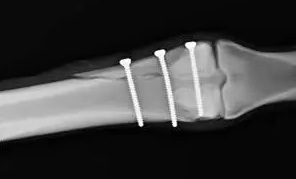

髄内固定

髄内スクリュー固定は、低侵襲性アプローチと良好な転帰に関するエビデンスの増加により、より一般的になっています。中手骨頸部骨折に関する最近のシステマティックレビューでは、順行性髄内固定(髄内スクリューが骨折の近位端に挿入される方法)は、保存的治療や逆行性髄内固定と比較して、より迅速な疼痛軽減と機能改善をもたらすことが報告されています。しかしながら、順行性髄内固定は、インプラントの移動や神経学的合併症のリスクが高くなる可能性があります。逆行性挿入法(髄内スクリューが骨折の遠位端に挿入される方法)は、良好な成績が報告されている新しい手技です。中手骨頭骨折では、遠位骨片の大きさが、髄内スクリューによる順行性固定において問題となる場合があります。逆行性挿入法は、遠位骨片をより確実に捕捉できるため、一部の外科医は、これをより簡便な手技であると述べています。

文献1】より